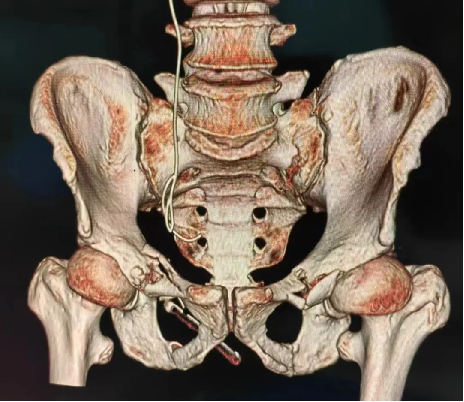

患者黃(huáng)某,因車禍外傷導致全身多處疼痛入院(yuàn),入院即因失血性休(xiū)克於ICU監(jiān)護,完善檢查顯示雙側恥骨粉碎性骨折、右側髂骨多處骨折、右骶髂關節脫位,提示骨盆前-後環均不穩定(dìng)。

對於此種前後環均嚴重失穩(wěn)的複雜(zá)骨盆(pén)骨折的治療,保守治療不僅需長期臥床,易導致褥(rù)瘡、肺部感染、泌尿(niào)係(xì)感染及深靜脈血栓風險,同時勢必影響後(hòu)期功(gōng)能恢複,嚴重降低患者未來生活質量。傳統開放術式手術切口大、手(shǒu)術時間長,手術難度極大,同時存在盆腔內血管神經及膀胱的醫源性損傷風險,以往,遇到此種嚴重(chóng)病情隻能依賴上級醫院專家來(lái)院手術指導,但基於(yú)近期成功開展的骨盆微創治療的經驗支持,外一科董(dǒng)明主任反複(fù)研究患者病情及影像,充(chōng)分(fèn)考慮手術創傷與(yǔ)風險後,決定開展(zhǎn)骨盆骨折(shé)有限切開複位(wèi)內固定術。